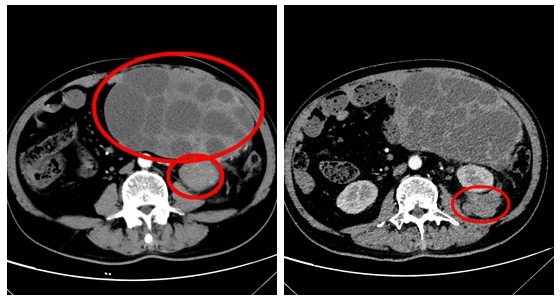

据悉,该患者因持续腹痛10余天来院就诊,经检查发现腹腔内存在多发肿物,较大者约(20×18cm),初步考虑为间叶源性肿瘤,但具体性质尚不明确。入院后,普外科医疗团队为患者进行了增强CT检查与穿刺活检,初步排除了胃肠道间质瘤及淋巴瘤的可能性,考虑诊断为脂肪肉瘤。患者经过多方打听和咨询,了解到廖国庆主任在胃肠道肿瘤领域的权威性,最终选择在湘雅常德医院进行手术治疗。

图中标识处为肿瘤

考虑到肿瘤体积巨大,且血供丰富,由肠系膜下动脉供血,另外在左肾周围另有两个稍小病灶(大小分别约4×4cm及4×8cm),与左肾关系密切,手术难度和风险极高,有可能需联合左肾切除,医院组织了多学科专家会诊,制定了周密的手术方案。2月18日,廖国庆教授团队为患者实施了腹膜后巨大肿物切除手术。手术过程中,廖教授团队克服了肿瘤与周围组织粘连严重、位置深、分离难度大等困难,成功完整切除了肿瘤,并有效控制了出血。